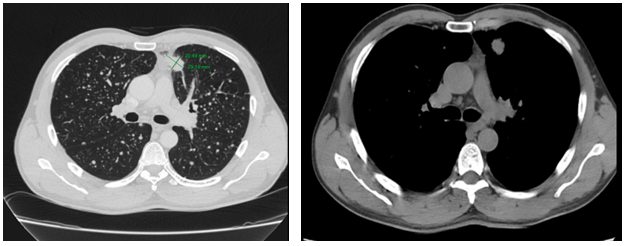

-         Cắt lớp vi tính lồng ngực:

Sau 3 tháng điều trị đích:

U nguyên phát và u thứ phát ở cả 2 phổi đều giảm kích thước rất nhiều, không thấy hạch trung thất.

Sau 6 tháng điều trị:

U nguyên phát chỉ còn kích thước rất nhỏ, u thứ phát 2 bên phổi đã mất hết.